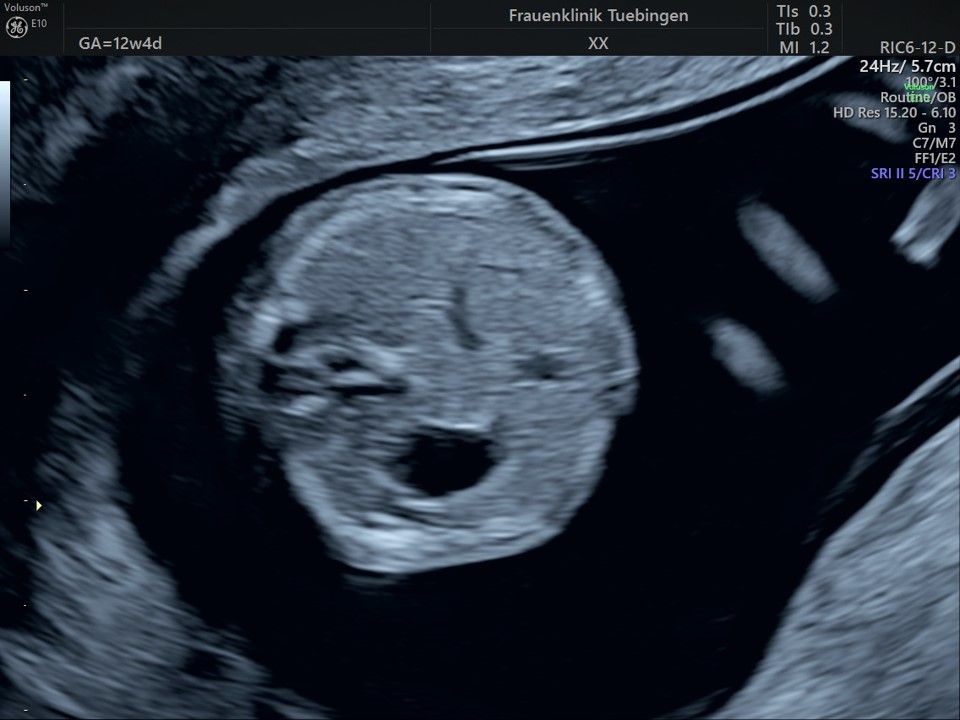

Im Rahmen des Ersttrimester-Screenings untersuchen wir die Organe des Feten mittels Ultraschall. Dabei machen wir auch gerne ein Bild für Sie.

Obwohl der Fet zu diesem Zeitpunkt erst zwischen 5 und 8cm groß ist, lassen sich bereits etwa die Hälfte aller schwerwiegenden Fehlbildungen erkennen bzw. ausschließen. Sollten wir eine Auffälligkeit sehen, werden wir mit Ihnen den Befund und das weitere Vorgehen ausführlich besprechen.

Fetale Anatomie